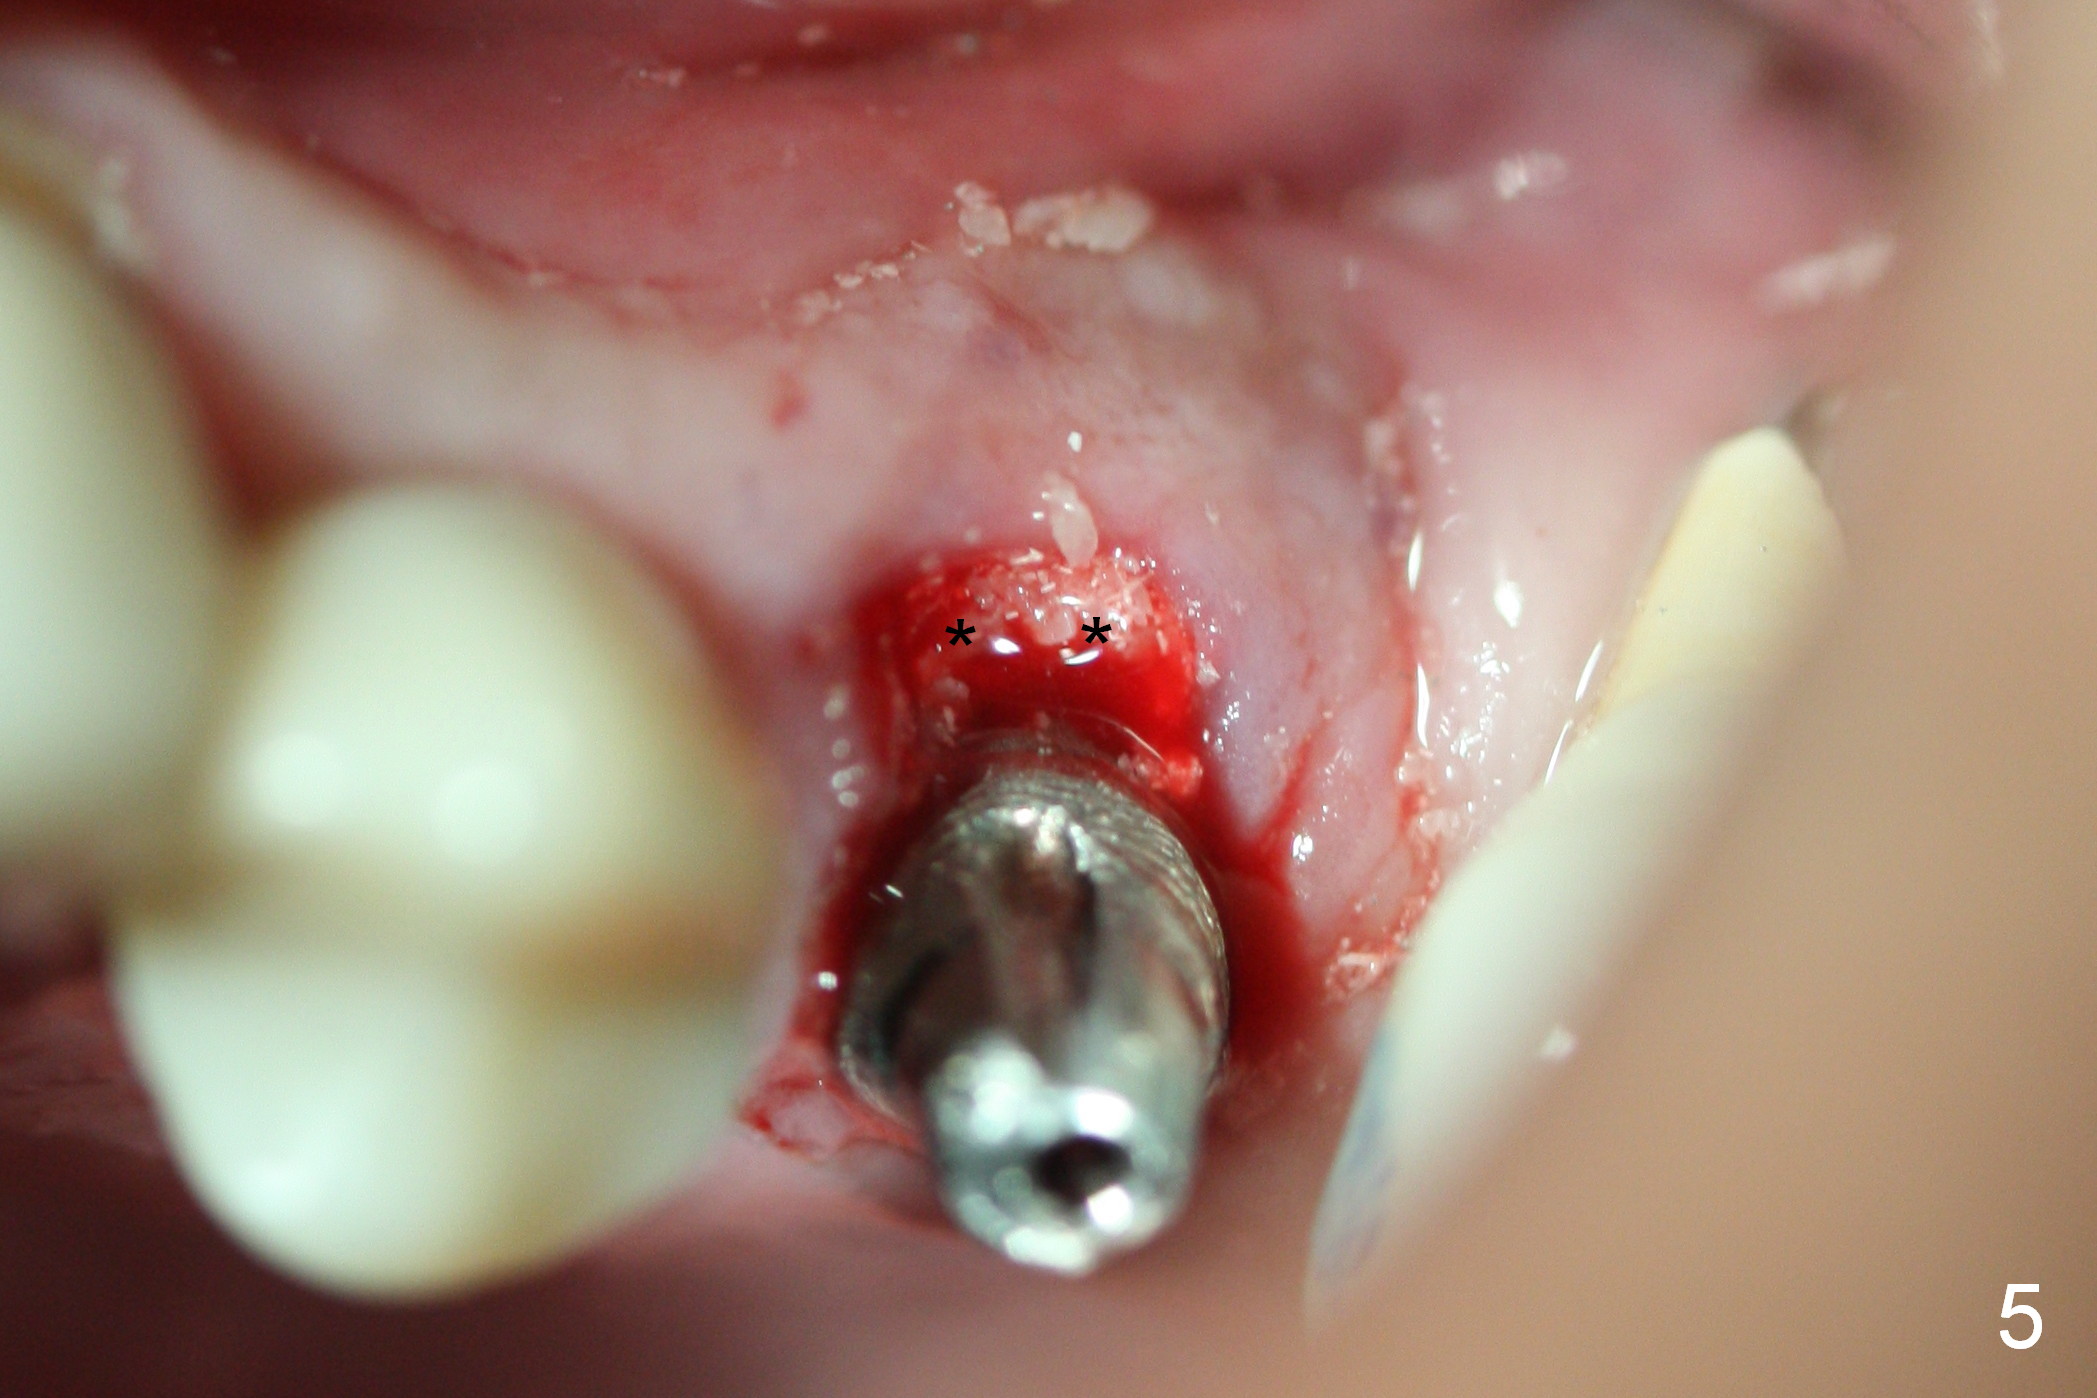

Extraction of the affected 2nd premolar is easy; the apical bone is so hard that drill and reamers have to be used for osteotomy, followed by insertion of a 4.5 mm tap with stability (Fig.1 T). The sinus floor (^) is lifted. There is no sign of sinus membrane perforation before placement of a 4.5x14 mm implant (Fig.2 I); sinus lift is performed (*: autogenous bone mixed with Mineralized Cancellous Human Allograft, Impladent); an immediate abutment (3.5x3 mm) is placed (A). With gauze placed in the buccal gap (Fig.3 G), the margin of the implant (I) is prepared for an immediate provisional fabrication. Mixture of autogenous bone (from reamers), allograft and Osteogen is placed in the remaining socket (Fig.4,5 *). When the relined (1st modification), trimmed and polished provisional is reseated (Fig.6 P), the bone graft (*) is not completely covered. New acrylic (2nd modification) is added to the margin of the provisional (Fig.7 *) for containment of the graft. There is almost no buccal plate; Osteotape (collagen membrane with Osteogen) is placed against the buccal wall of the socket prior to bone grafting. The remaining small pieces of the Osteotape (Fig.7 <) are laid over the bone graft before reseating the final provisional. With "complete socket seal", perio dressing is unnecessary.